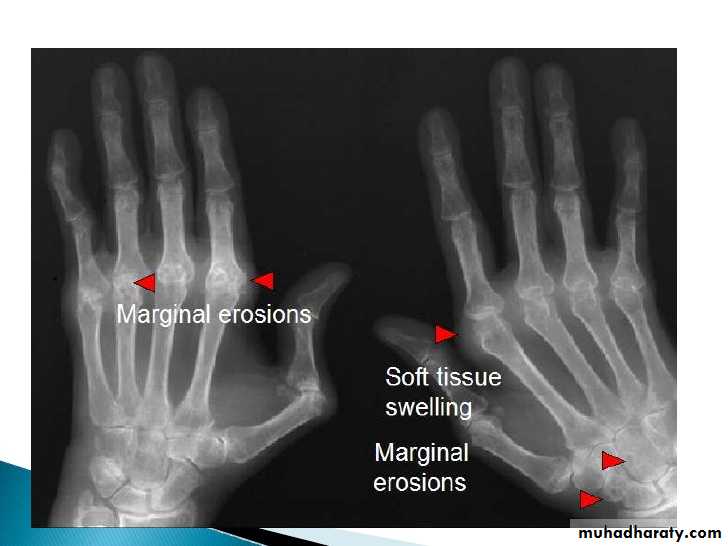

Earliest signs include

1.soft tissue swelling due to effusion, tenosynovitis, and edema2.Symmetric Periarticular osteopenia

3.Marginal erosions often first seen at 2nd and 3rd MCPs and 3rd PIP articulations

Preferred sites of early involvement:

Hand: 2nd & 3rd MCP jointsFoot: 4th & 5th MTP joints